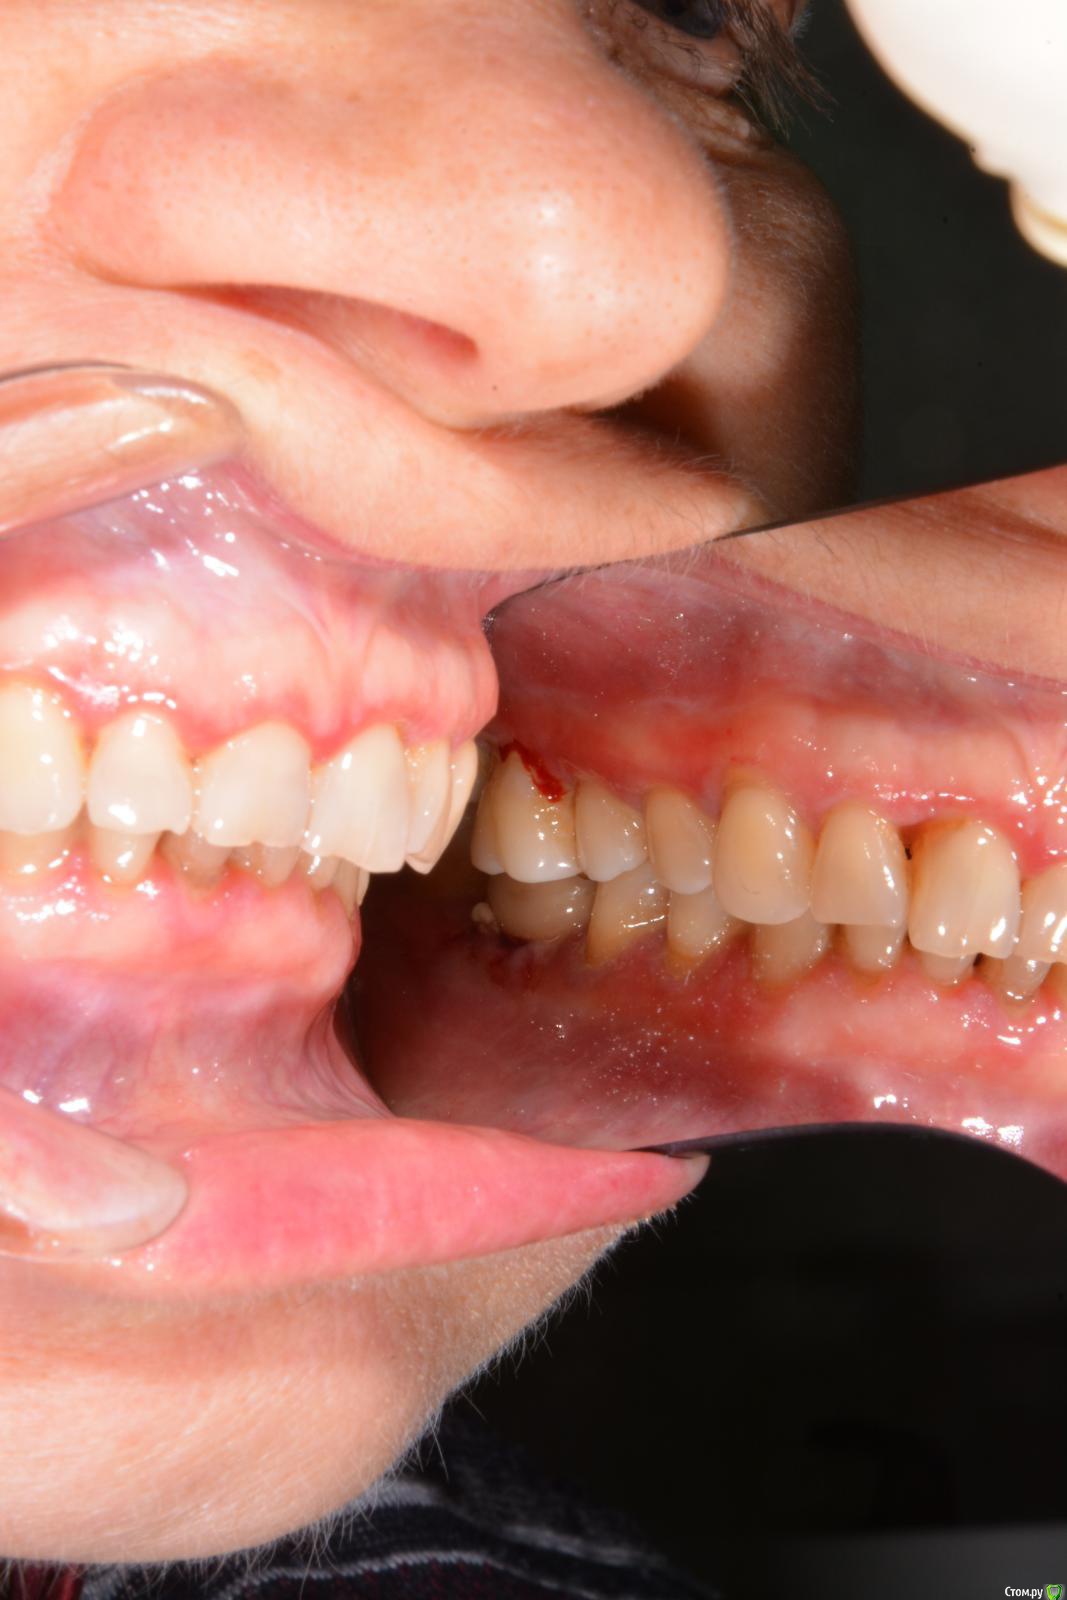

Руслан Аминов Опубликовано 6 ноября, 2019 Поделиться Опубликовано 6 ноября, 2019 Имплант Adin в области зуба 36, установлен в 2015 году. Шахта имплантата выходит язычно. Установлена коронка м/к на абатменте. Коронка расфиксировалась месяц назад, в клинику пациент не обращался. Сейчас десна гиперемирована, отечна, кровоточит при зондировании, при пальпации гноетечение. На Rg кость резорбировалась до 3 витка. На приеме почистили, помыли хг, коронку обработали и зафиксировали на временный цемент. Через неделю ситуация не улучшилась. Подскажите как снять воспаление. Имеет ли смысл проводить мягкотканную пластику? или удаление импланта? Ссылка на комментарий

red_butler Опубликовано 6 ноября, 2019 Поделиться Опубликовано 6 ноября, 2019 На приеме почистили что именно? ваши фото не информативны Ссылка на комментарий